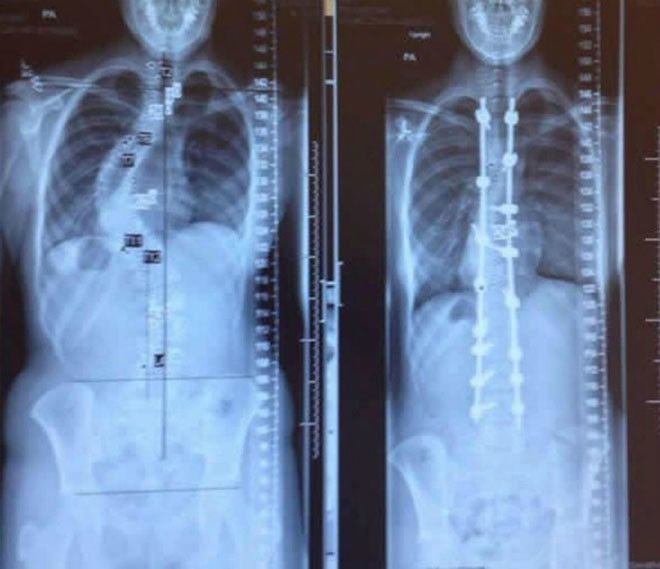

До и после лечения сколиоза

Эти снимки демонстрируют удивительные изменения позвоночника до и после лечения сколиоза.